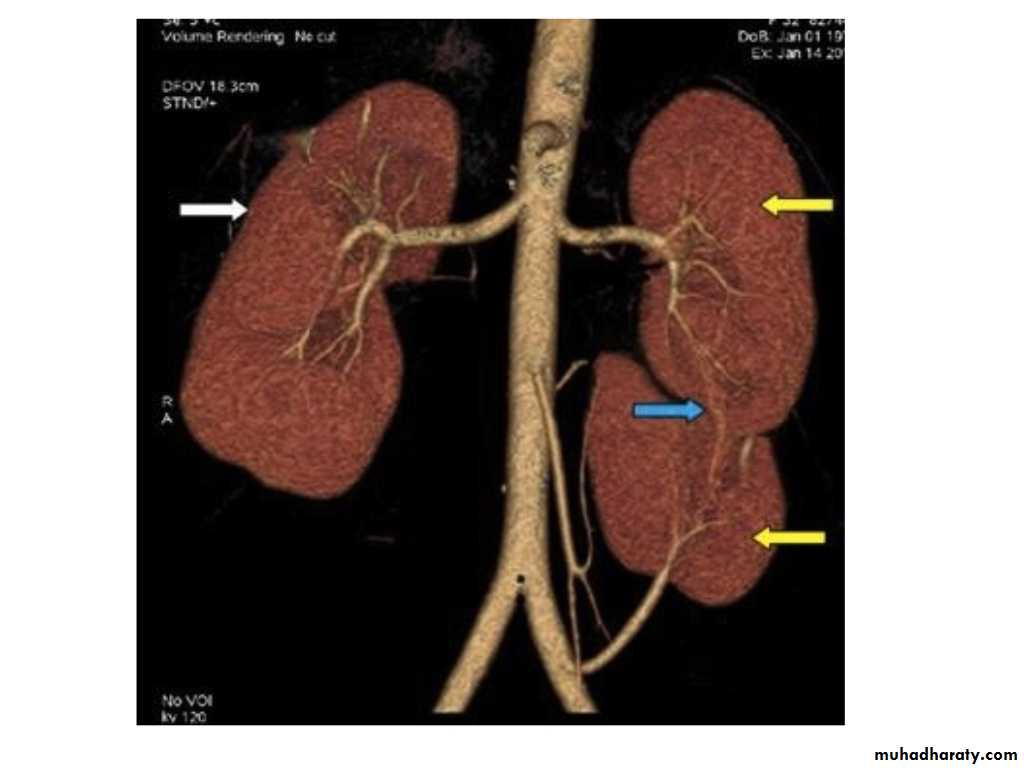

IVU shows

1. The kidneys at low position .2.Close to the spine with long axis parallel to the spine

3. Malrotation manifested by medially directed calyces.

4- The renal pelvis and ureters are anterior and lateral in position.

5- Hydronephrosis and calculi highly associated.